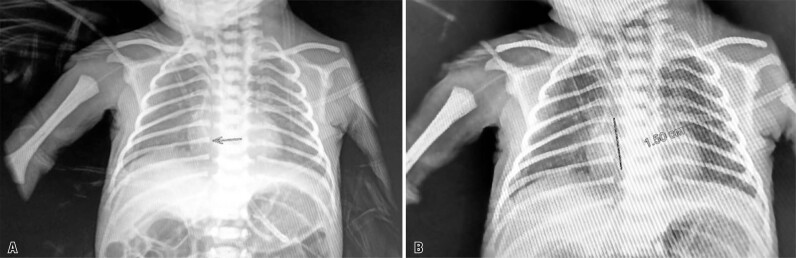

背景:这篇文章描述了在巴西的一所大学医院,一个早产儿在使用外周插入中心导管后发生心脏填塞。行心包穿刺,经x线摄影重新定位导管,超声心动图证实心包积液残留极小。患者进展良好,并于生命第47天出院,无任何与该事件相关的并发症。因此,尽管在置入外周中心导管后可能发生不良事件,但影像学检查和排除诊断对临床结果有积极影响。本研究强调了多学科团队对监测和管理不良事件以及优化危重新生儿护理的重要性。

Background: This article describes the occurrence of cardiac tamponade in a premature newborn after the use of a peripherally inserted central catheter at a university hospital in Brazil. Pericardiocentesis was performed, the catheter was repositioned using radiography, and minimal residual pericardial effusion was confirmed using echocardiography. The patient showed good progress and was discharged from the hospital on day 47 of life without any complications related to the event. Therefore, although adverse events may occur following the insertion of peripherally inserted central catheters, imaging examinations and exclusion diagnoses have a positive impact on clinical outcomes. This study emphasizes the importance of a multidisciplinary team for monitoring and managing adverse events and optimizing the care of critically ill newborns.